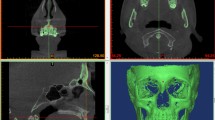

Intra-operator reproducibility of the visually segmented surface models was tested at three levels, similarly to a previously applied method2. First, the mean absolute distance (MAD), as well as the standard deviation of the absolute distances (SDAD), of the repeatedly extracted models was calculated, considering the distance of each vertex point of one mesh model to the closest point on the second model, at three predefined measurement areas consisting of 2000 triangles each. For this assessment, the segmented surface models retained their spatial relations in the source radiographic volume. The measurement areas were located on the forehead, the zygomatic process, and the maxillary complex, bilaterally. The bilaterally selected triangles on each anatomical structure were considered as one measurement area (Fig. 2A). Colour coded distance maps between repeatedly segmented entire models were generated to represent the cases with minimum, average and maximum difference on all measurement areas. Afterwards, each pair of repeated models was superimposed through a variant of the iterative closest point (ICP) algorithm26, under the following software settings: 100% estimated overlap of meshes, matching point to plane, exact nearest neighbour search, 100% point sampling, 50 iterations. The used superimposition reference area is shown in Fig. 2C. The rotational and translational movements required for the best fit approximation of each pair of models were recorded to describe differences between their original position and the position after superimposition. Finally, the MAD (SDAD) between the superimposed models at the pre-defined measurement areas was calculated to test their morphological differences, independent of their position in space. Zero MAD prior to superimposition and zero movements were considered as perfect reproducibility.

(A, B). Three measurement areas defined in each skull through bilaterally selected mesh surfaces at the forehead (blue), the zygomatic process (green), and the maxillary process (red) for reproducibility and trueness assessment, respectively. Each circular area shown in the images consists of 1000 triangles. (C). Reference area (light blue) used for all surface-based superimpositions performed in the study.

Trueness of radiographically derived surface models

The trueness of the radiographically derived skeletal surface models was tested through comparison with directly obtained models using a high-accuracy optical surface scanner20,22. For this purpose, each radiographically derived surface model was best-fit approximated to its corresponding optical scanner derived model, using the same settings and reference areas described above, regarding the intra-operator reproducibility of the visually segmented surface models. The congruence of the superimposed models on three pre-defined measurement areas, consisting of 4,000 triangles each, was calculated as MAD (SDAD) and this was the metric to assess trueness. The measurement areas were placed bilaterally on the forehead, the zygomatic process, and the maxillary complex. The bilaterally selected triangles on each anatomical structure were considered as one measurement area (Fig. 2B). These measurement areas were selected only once for each skull, on the optical scanner derived surface, and were used for all comparisons to eliminate confounding due to measurement area selection. Colour coded distance maps between superimposed entire models were generated to represent the cases with minimum, average and maximum difference on all measurement areas. Zero difference between the superimposed models indicates perfect trueness.